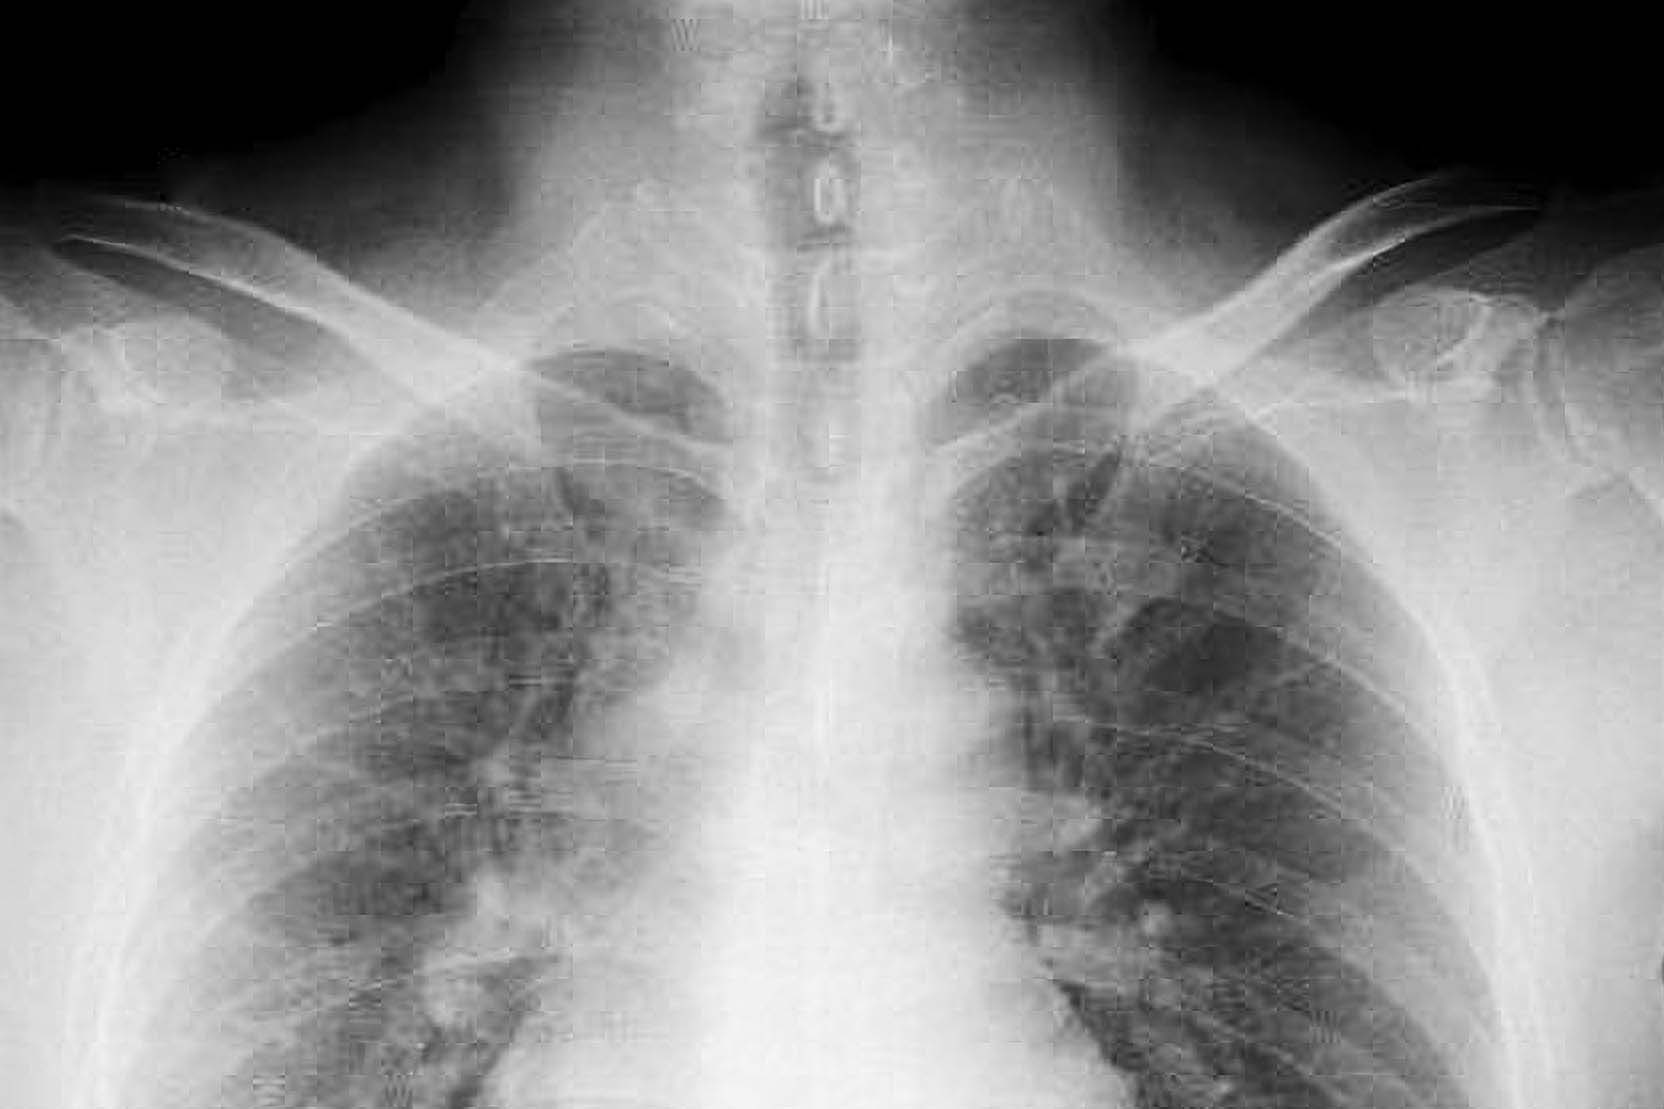

恩主公醫院胸腔外科主任陳右儒分享,這起令人印象深刻的臨床案例。一名80多歲老婦人因跌倒外傷接受電腦斷層掃描,意外發現肺部異常,確診為早期肺腺癌,這場「意外」也讓兩位女兒主動接受低劑量電腦斷層(LDCT)篩檢。

結果顯示,警覺心真的救了她們。50多歲的大女兒初次篩檢發現微小結節,追蹤兩年後病灶增大至1.55公分,雖無症狀,但考量家族史風險,經評估後手術確診為極早期肺腺癌;另一名50多歲的女兒則發現癌前病變(非典型腺體增生)。幸運的是,母女三人都在早期階段介入,術後恢復良好,生活未受影響。

隨著科技進步,影像檢查已結合AI輔助標示可疑訊號,但陳右儒澄清,被AI標示不代表就是癌症,這僅是降低遺漏的輔助手段。

最終診斷仍需仰賴放射科與臨床醫師的綜合判讀,甚至透過病理切片確認。民眾若發現肺結節無須過度恐慌,並非所有結節都需立刻動刀,關鍵在於與信任的專科醫師討論,決定是持續追蹤觀察或進一步治療。